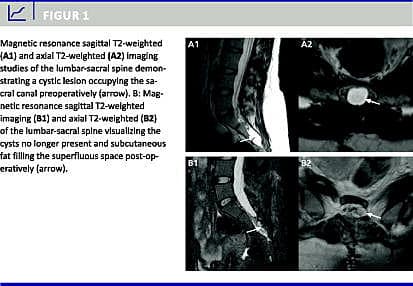

En spinal nerverodscyste diagnosticeres med magnetisk resonans (MR)-skanning. Prævalensen er estimeret til 1-4,6%, og heraf er cirka en femtedel symptomatiske. Flertallet er kvinder. Cysterne findes hyppigst sakralt, og deres lokalisation medfører radikulopati samt urin-, tarm- og seksuel dysfunktion. Vi præsenterer her vores mikrokirurgiske procedure som behandlingsmetode og redegør for kliniske resultater.

I perioden fra januar 2006 til maj 2010 blev 12 patienter med i alt 23 cyster, alle kvinder, opereret for 20 symptomatiske spinale nerverodscyster. Gennemsnitsalderen var 45 (13-75) år. Alle patienter gennemgik en præoperativ MR-skanning. Komorbiditet blev udelukket som årsag til symptomerne. Postoperativt blev alle fulgt i op efter tre måneder. Yderligere followupundersøgelse blev tilbudt, når det var indiceret.